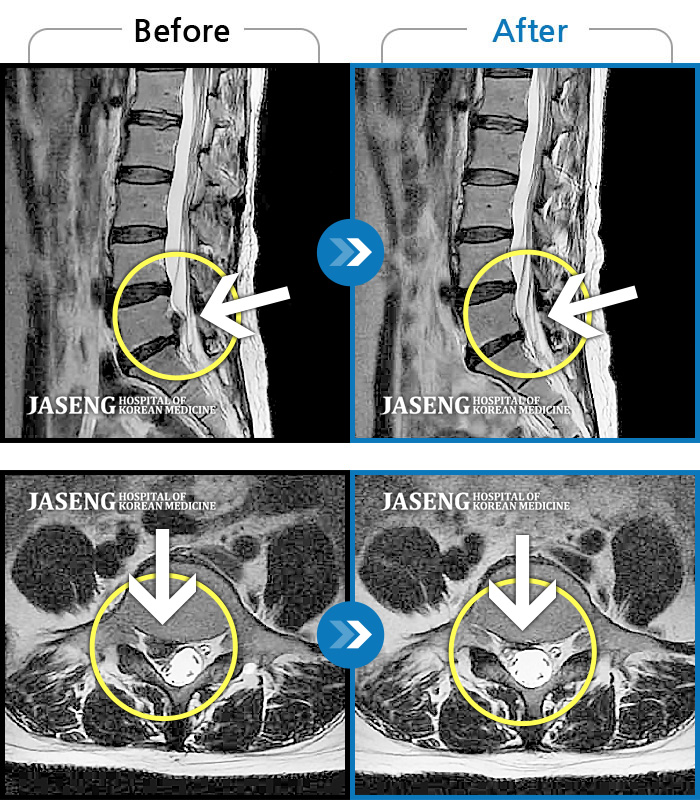

허리디스크

수원 · 김태성 원장

허리 통증과 좌측 대퇴부 저림과 당김

촬영시기

2023.02.03 ~ 2024.02.14

2024.11.21